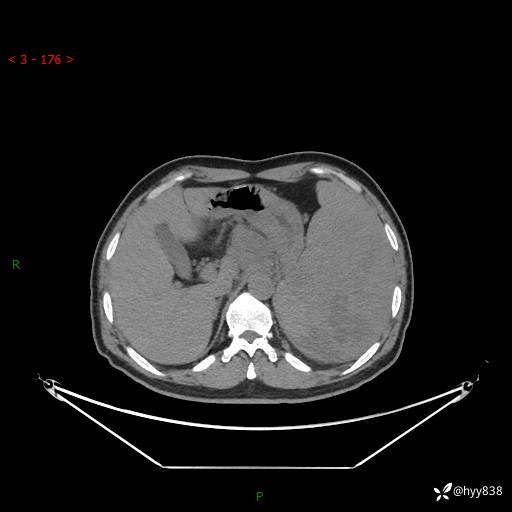

上腹部CT平扫

增强(动脉期+静脉期)